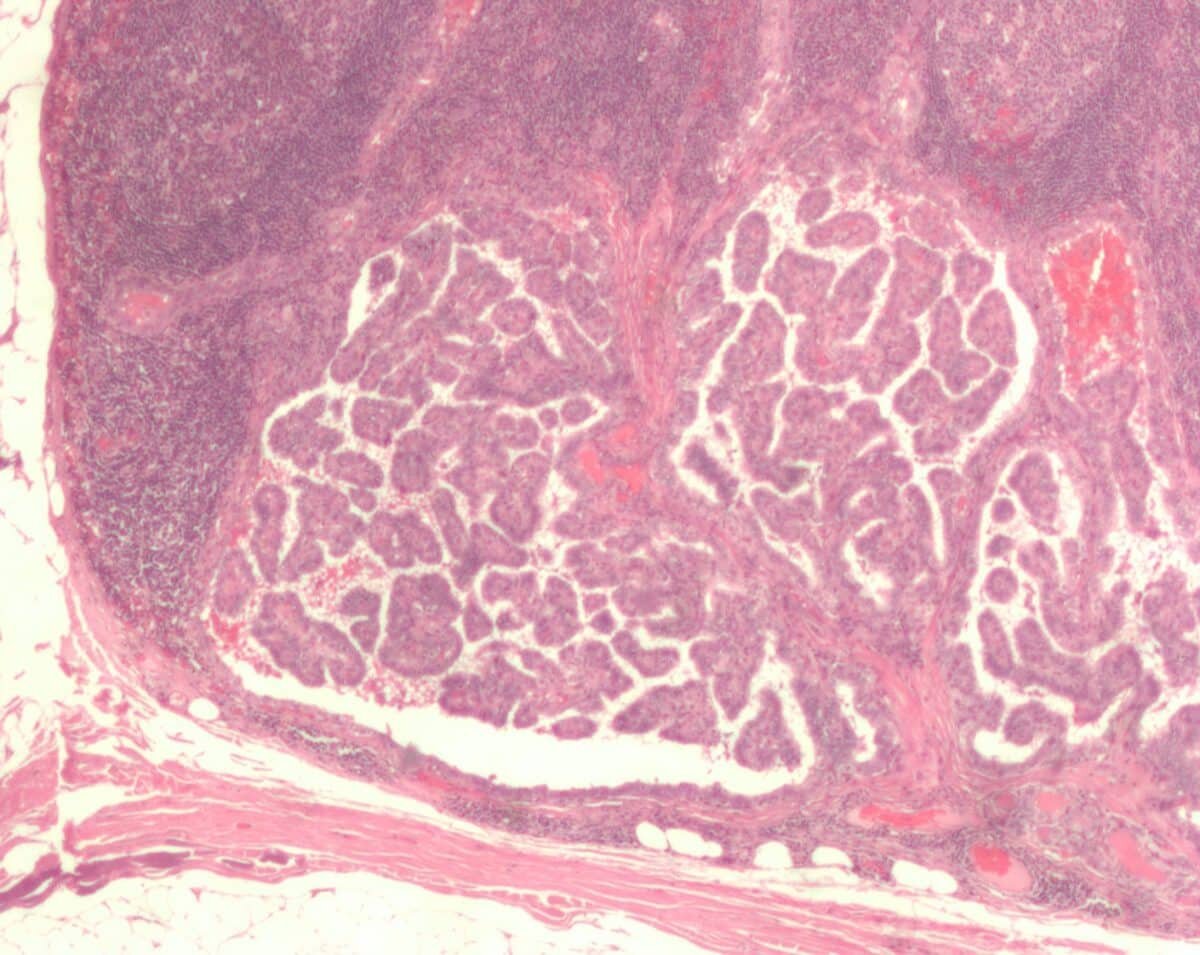

Метастатическое поражение лимфатического узла при папиллярном раке щитовидной железы. Микрофотография / © Nephron / Wikipedia

По своей сути, онкологическое заболевание — это внутренняя «поломка». Здоровая клетка следует строгой программе: растет, работает и, состарившись, умирает. Рак начинается, когда одна клетка нарушает эту последовательность. Она перестает быть частью слаженной системы и начинает бесконечно копировать саму себя. Позже из нее образуется множество таких же «испорченных» элементов, формирующих опухоль. Это образование способно прорастать в соседние здоровые ткани и отправлять свои «клоны» с током крови или лимфы в другие органы, создавая новые очаги болезни — метастазы.